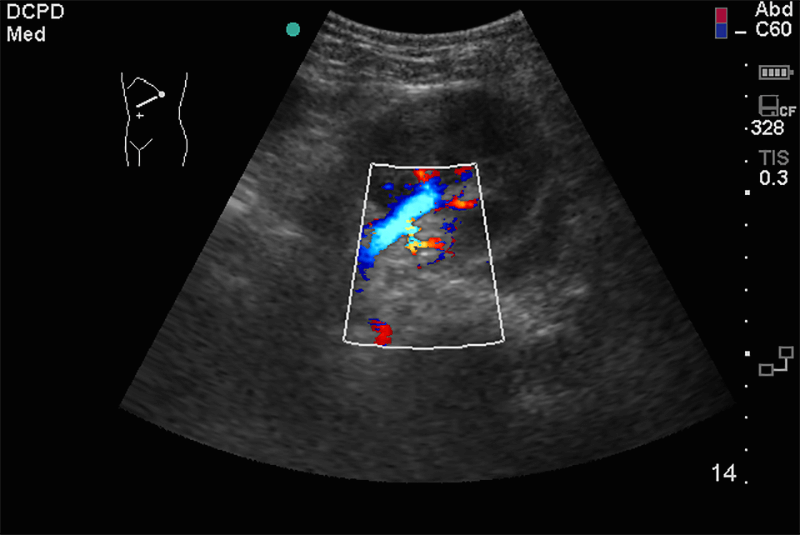

Doppleres érvizsgálatok az erek tágassága, faluk állapota, lefutása mellett, színes és pulzus dopplerrel vizsgálható bennük a keringés iránya, mérhető a keringés sebessége.

A kóros tágulatok és szûkületek, thrombusok, az erek részleges vagy teljes elzáródása kimutatható, mérhető. Érvizsgálataink a nyaki (carotis) erek állapotának tisztázására vonatkoznak.

Az érelmeszesedés korai stádiumban való felismerése a súlyos szövődmények megelőzése érdekében rendkívüli fontossággal bír. A már kialakult érbetegségekben az ultrahang a terápia megválasztásához feltétlenül szükséges.